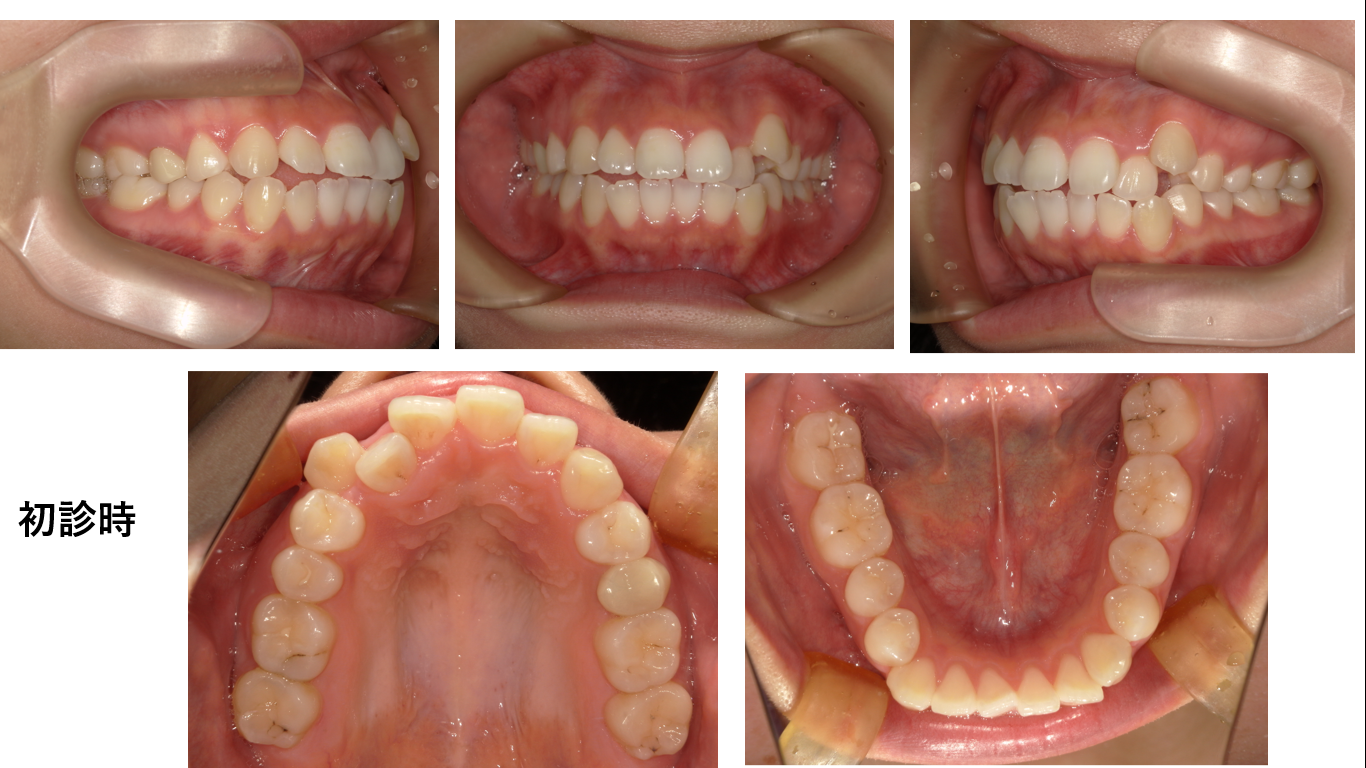

矯正症例135 AngleⅠ級叢生

初診時21歳、治療期間2年8か月、抜歯部位:上下顎左右4番、治療費総額121万(税込み)歯列矯正には以下のリスクを伴う場合があります。1最初は矯正装置による不快感、痛み等があります。数日間~1、2 週...